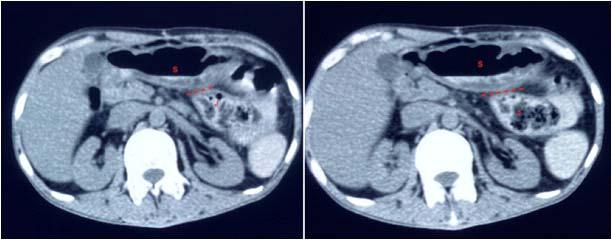

Among the metabolically abnormal patient’s population 20% (n=3) had Hypoglycemia, 40%(n=6) presented with Dyselectrolytemia, 26.67% (n=4) had Uremia, 13.33% (n=2) presented with Hepatic encephalopathy. Overall, 31 patients underwent Lumber puncture, of which CSF report shows abnormality in 11 (35.48%) cases and normal in 20 patients (64.51%). Abnormal CSF report suggesting viral meningoencephalitis found in 46% (n=5), bacterial meningitis in18% (n=2), Tuberculous Meningitis in 27% (n=3), Aseptic meningitis in 9% (n= 1). All 65 subjects underwent CT scan brain among which MRI Brain also done in 55 cases. CT findings is normal in 44.62% (n=29), abnormal in 55.38% (n=36). The most common CNS lesion on CT scan was infarction in 10.77% followed by ring lesion in 9.23% and intracerebral Hemorrhage in 7.96%. We observed cerebral infarction is causative factor of Seizure in female (15%) but intracerebral hemorrhage and ring lesion are most common findings in male, comprising 11.11% patients at each category. The CT scan in new onset Seizure of elderly patient population revealed Infarction in 28.57%, Gliosis in 19.04% and cerebral atrophy in 14.28%. The breakup of findings in MRI Scan of 55 patients shows Hyperintensities on T2, indicating Demyelination / Inflammation/edema in12.31% followed by infarction in 10.77% and ring lesion in 9.23%. In the female population, hyperintensities on T2 MRI found in 15% and Infarction in 15% whereas among the males intracerebral Hemorrhage, Ring lesion and hyperintensities on T2 found at similar occurrence rate @11% in each of these three types of lesions. EEG was done on 80% patients (n=52) of whom 22 patients has abnormal discharge in EEG but 30 patients have normal presentation. Among 65 patients one female expired due to Acute Demyelinated Encephalomyelitis (ADEM) and two males expired one due to Hemorrhage, another one with CNS infection when undergoing treatment indoor.

We found a strong positive correlation between abnormal EEG and abnormal Neuroimaging with Correlation coefficient of 0.902, (P- Value 0.0138) but almost no correlation found between normal EEG with normal Neuroimaging (Figs 1-4).

About 23% of patients with adult onset first seizure has metabolic derangement and the most common etiology was Dyselectrolytemia. The most common Central Nervous System (CNS) Infection as detected by CSF study was viral meningoencephalitis followed by Tuberculous Meningitis. The most common CNS lesion detected by CT studies as well as by MRI Brain was infarction and ring lesion, the two Neuroimaging studies corroborated in 75.38% of Seizure patients. Abnormal discharge in EEG found in34% cases. In majority patients EEG report was normal. EEG abnormality was more common in patients with Focal Seizure rather than GTCS patients. Thus, the most common etiology of first Seizure onset at adult age over 18 years were metabolic derangements (16.92%), CNS Infection or Inflammation (15.38%) and intracerebral Space occupying lesion (15.38%), usually ring lesion, tumors and Metastasis. Idiopathic Seizure found in 7.69% patients. The Correlation between abnormal Neuroimaging and abnormal EEG is strongly positive and statistically significant (P -Value = 0.013) but the same is not true in cases of normal Neuroimaging and normal EEG findings.